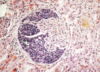

What are some key features of this chromophobe renal cell carcinoma?

Lacks a central scar BUT is well circumscribed with a brown hue

What is shown in this image?

• what are some KEY features?

Renal Cell CHROMOPHOBE carcinoma

- Clearing (HALO) around the nuclei = another key feature to look for in addition to Hale’s colloidal for differentiating this from oncomocytoma

- Distinct cell membranes